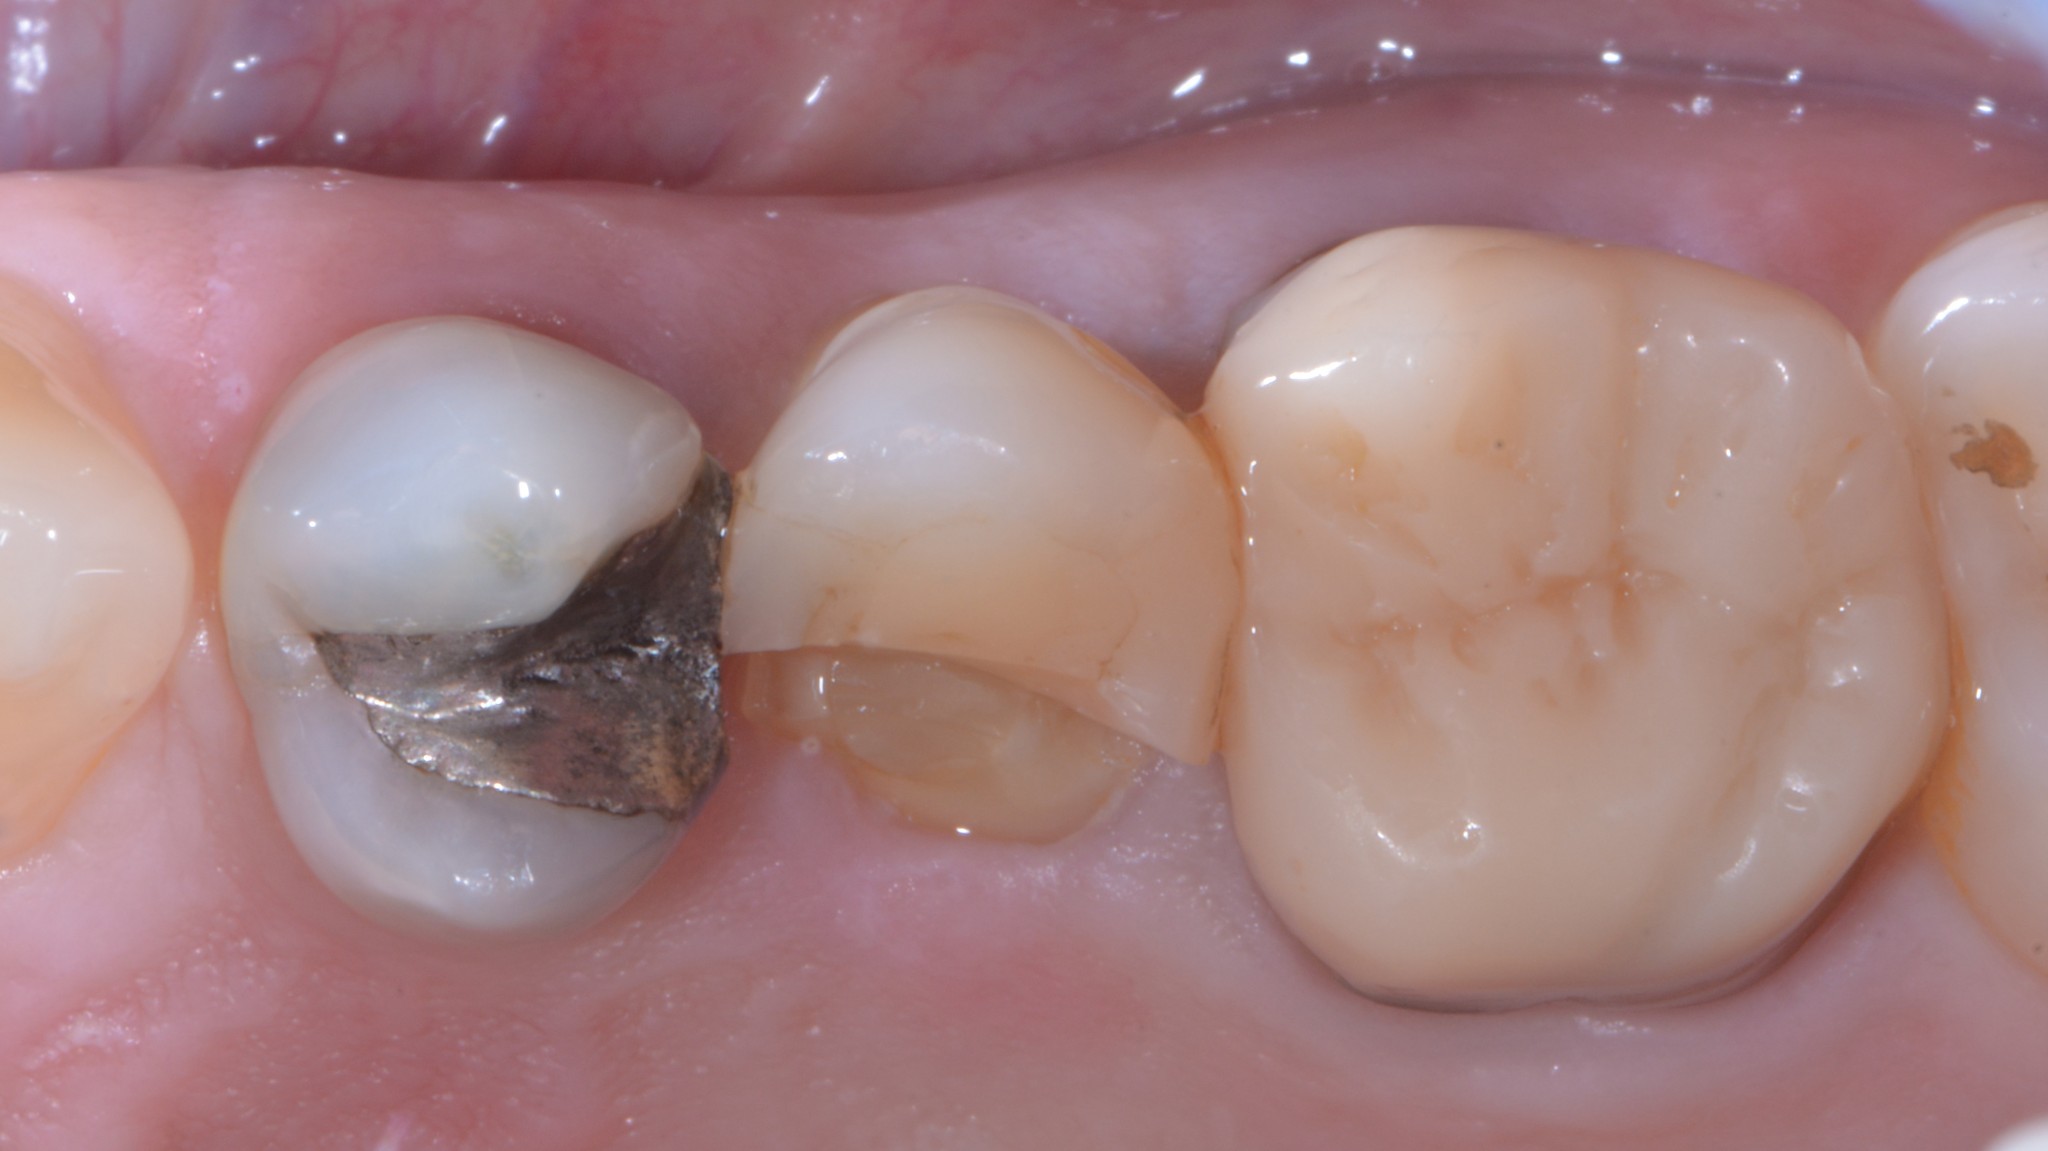

Ecco cosa succede:

Frattura coronale complicata con margine di frattura sottogengivale di almeno tre millimetri.

Spesso capita che i premolari e i molari superiori si fratturino dal lato palatino. In questi casi possiamo eseguire un allungamento che si limita a quell’aspetto in modo da preservare l’estetica vestibolare pur mantenendo l’imprescindibile condizione di un’anatomia positiva della festonatura gengivale.